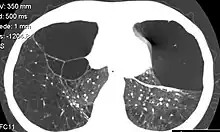

| CT scan of the lung showing bullae in the lower lung lobes of a subject with type alpha-1-antitrypsin deficiency. There is also increased lung density in areas with compression of lung tissue by the bullae. | |

A focal lung pneumatosis, is an enclosed pocket of air or gas in the lung and includes blebs, bullae, pulmonary cysts, and lung cavities. Blebs and bullae can be classified by their wall thickness.[1]

- A bulla has a wall thickness of less than 1 mm.[2] By radiology definition, it has a total size of greater than 1 cm.[3] By pathology definition, it originates in the lung parenchyma (rather than in the pleurae).[4]